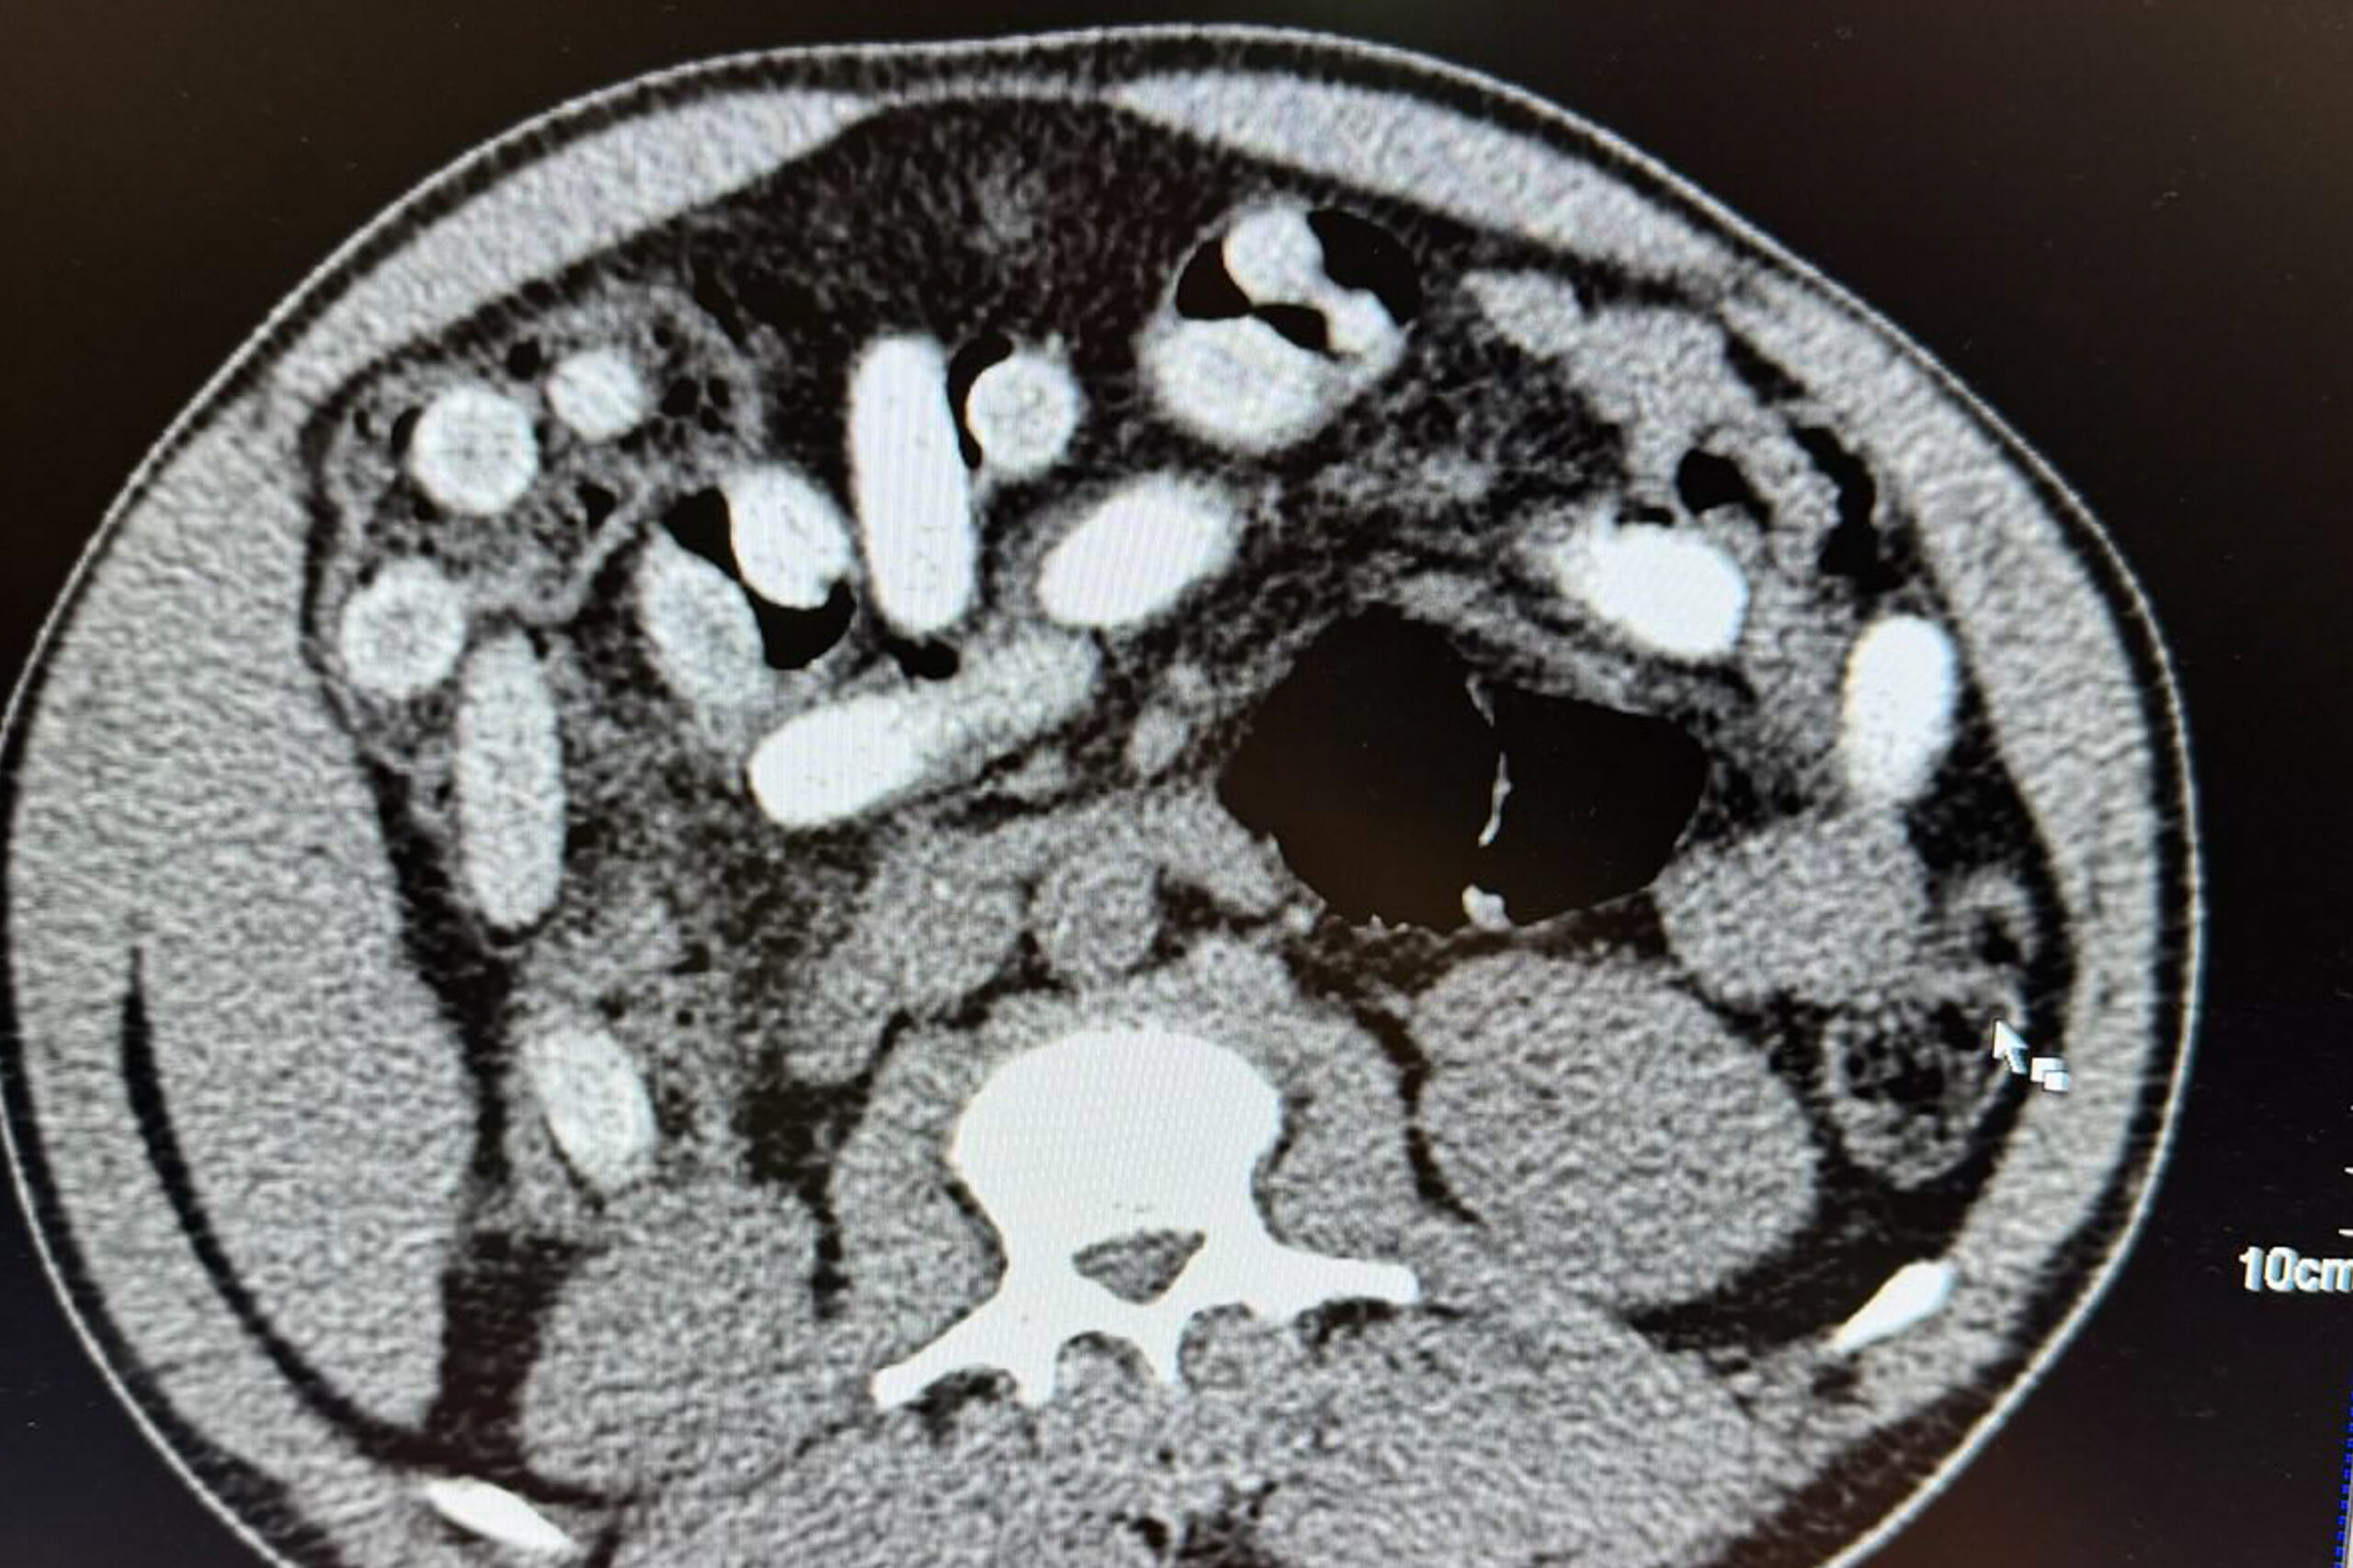

Ein Drogenwischtest an den Handinnenflächen reagierte positiv auf Kokain. Daraufhin wurde der Mann in ein nahegelegenes Krankenhaus gebracht. „Die Röntgenaufnahme bestätigte letztlich den Verdacht. Der komplette Magen-Darm-Trakt war gefüllt mit Drogenpäckchen, sogenannten Bodypacks“, erklärte Jens Ahland, Pressesprecher des Hauptzollamts Köln. Die 111 geschluckten Päckchen – in Größe und Form mit Datteln vergleichbar – enthielten insgesamt rund 1,3 Kilogramm Kokain. „Das Risiko ist enorm. Platzt nur ein Päckchen im Körper, kann das tödlich enden, selbst wenn ein Arzt anwesend ist“, so Ahland.